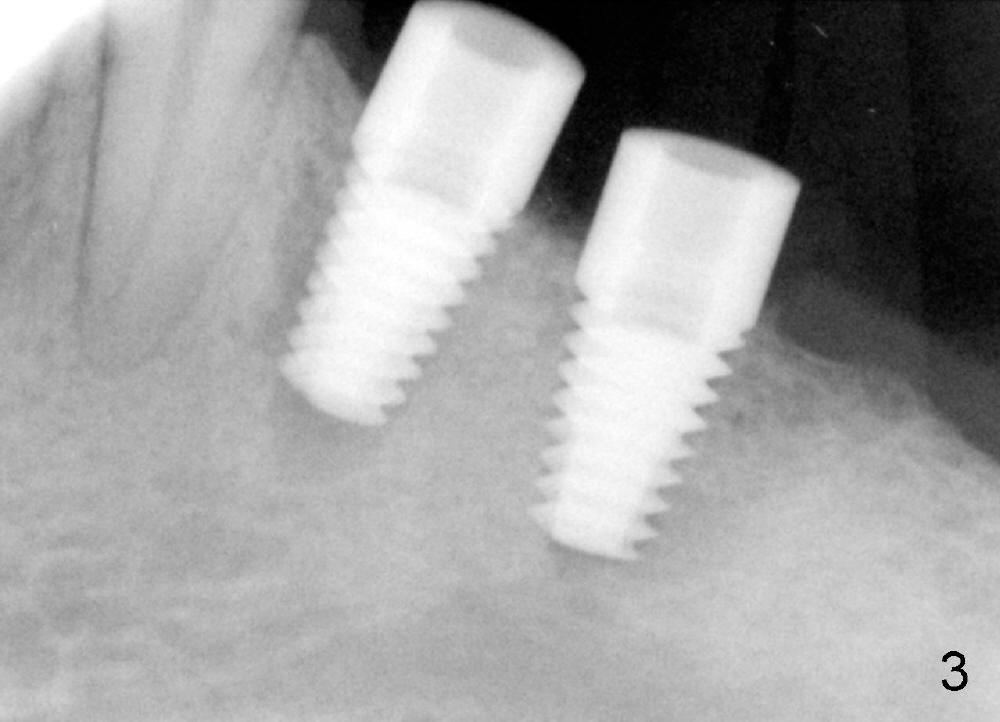

Two implants are to be placed at the sites of #20 and 21 (Fig.1 CT sagittal section) to be used as ortho anchorages. When paralleling pins (Fig.2 P) are inserted, they happen to be in the original sockets (arrowheads). Two 4.5x11 mm implants are also placed more or less in the original sockets (Fig.3). Postop X-ray is shown. Two separate provisional crowns are to be fabricated with the occlusal table of #20 being lower, since #13 has mobility and has supraerupted. Leave a space (1-2 mm) mesial to #21 provisional so that the tooth #22 and 23 can be moved distally. A premolar band is going to be placed at #21. There is no bone loss 2.5 years (Fig.4) or 3 years 9 months (Fig.5,6 CT) post cementation. Return to Implant & Ortho Full Mouth Reconstruction 3 24/26 28 30 Xin Wei, DDS, PhD, MS 1st edition 10/04/2014, last revision 12/16/2018